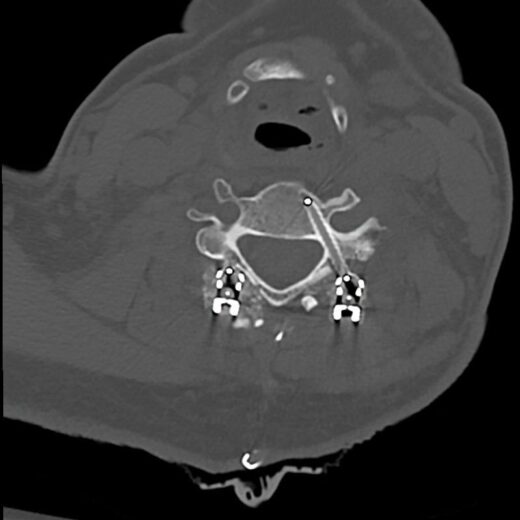

The CMORE® Cervicothoracic (CT) System is an enhanced set of instruments and implants for posterior stabilization of the cervicothoracic spine. The world’s first spinal implants made of nonmetallic and radiolucent BlackArmor® technology now enable a full spectrum of treatment modalities in adjuvant tumor therapy and enhance postoperative imaging diagnostics in the cervicothoracic spine.

- BlackArmor® material is radiolucent in all diagnostic imaging modes and facilitates adjuvant radiation treatment

- The first tulip made of BlackArmor® material for artifact-free CT and MRI imaging